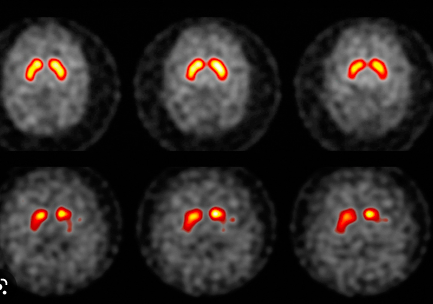

What imaging is used in this picture? [1]

dopamine transporter (DaT) - DaT scan